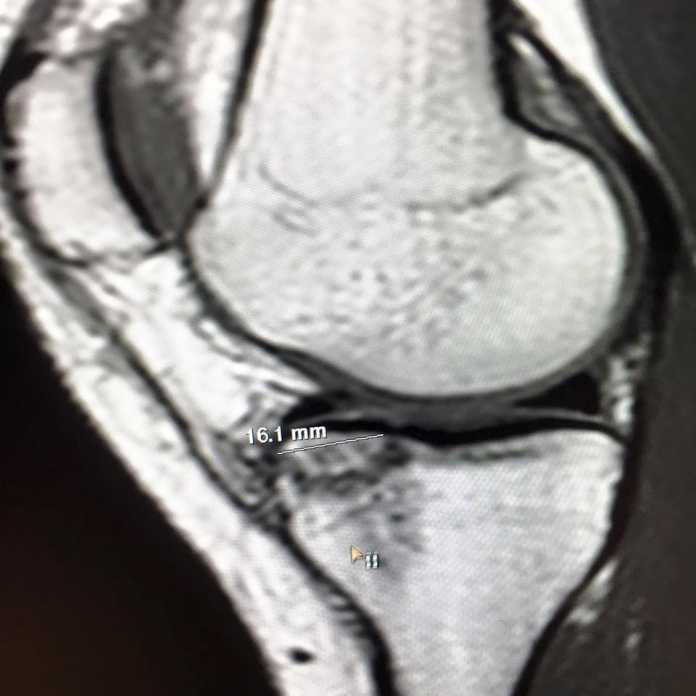

PAROLA DI LINDSEY – Vonn ha rimandato al mittente le accuse di tifosi austriaci e svizzeri che l’accusavano di essere un’attrice rispondendo ad alcune domande per RSI e ORF. Poi ha mostrato i risultati della risonanza magnetica su Facebook: «La risonanza mostra una bella frattura del mio piatto tibiale. Il legamento collaterale mediale sembra decente come pure il resto del ginocchio. Ora parlerò con il mio staff e decideremo un piano d’azione. Vi terrò aggiornati, grazie a tutti coloro che mi supportano sempre».